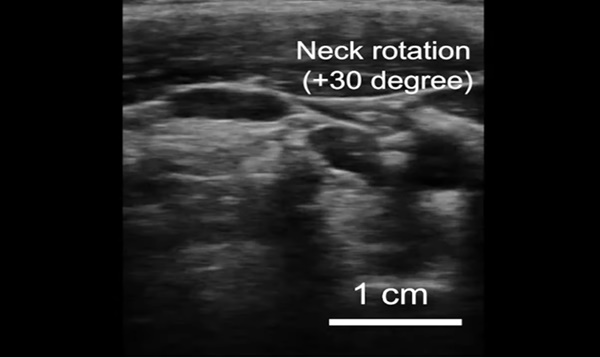

연구원들은 이 스티커를 건강한 자원자들의 목, 가슴, 복부, 팔을 포함한 몸의 다양한 부분에 붙이고 작동시켜 일련의 테스트를 했다. 그 결과 주요 혈관과 심장, 폐, 위 같은 몸속 더 깊은 곳에 있는 장기의 고해상도 이미지를 실시간으로 볼 수 있었다.

스티커들은 48시간 동안 시험 대상자들의 피부 아래 구조들의 선명한 이미지를 만들어 냈다. 스티커를 부착한 자원자는 앉기, 서기, 조깅, 자전거 타기, 역기에 이르기까지 다양한 활동을 실험실에서 수행했다. 스티커는 그동안 이들의 몸속에 있는 장기의 변화하는 모습을 포착해 보여 주었다.

연구팀은 스티커에서 나오는 이미지를 통해 앉았을 때와 서 있을 때 주요 혈관의 직경이 변하는 것을 관찰할 수 있었다. 이 스티커들은 또한 운동하는 동안 심장이 어떻게 운동하면서 모양을 바꾸는지와 같은 더 깊은 장기의 세부 사항들도 포착했다. 위가 팽창하는 것을 볼 수 있었고, 술을 마신 이들의 위가 다시 위축되는 것도 볼 수 있었다.

그리고 연구팀은 몇몇 자원자는 역기를 들 때 피부 아래 근육의 일시적 미세 손상을 나타내는 밝은 패턴을 발견할 수 있었다.

연구팀은 “우리는 이미징을 통해 운동을 과도하게 하기 전에 그 순간을 포착할 수 있고, 근육이 아프기 전에 멈출 수 있을지도 모른다. 우리는 아직 그 순간이 언제일지 모르지만, 이제 우리는 전문가들이 해석할 수 있는 이미징 데이터를 제공할 수 있다”고 말했다.